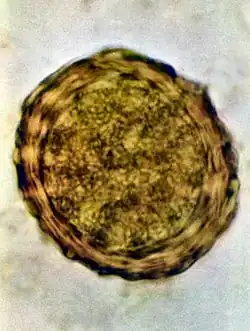

Ascaris lumbricoides is characterized by its great size. Males are 2–4 mm (0.08–0.2 in) in diameter and 15–31 cm (5.9–12 in) long. The male's posterior end is curved ventrally and has a bluntly pointed tail. Females are 3–6 mm (0.1–0.2 in) wide and 20–49 cm (7.9–19 in) long. The vulva is located in the anterior end and accounts for about one-third of its body length. Uteri may contain up to 27 million eggs at a time, with 200,000 being laid per day. Fertilized eggs are oval to round in shape and are 45–75 μm (0.0018–0.0030 in) long and 35–50 μm (0.0014–0.0020 in) wide with a thick outer shell. Unfertilized eggs measure 88–94 μm (0.0035–0.0037 in) long and 44 μm (0.0017 in) wide.[9]

A. lumbricoides eggs are extremely resistant to strong chemicals, desiccation, and low temperatures. The eggs can remain viable in soil for months or even years.[9] Eggs of A. lumbricoides have been identified in coprolites in the Americas, Europe, Africa, the Middle East, and New Zealand, the oldest ones being more than 24,000 years old.[12]